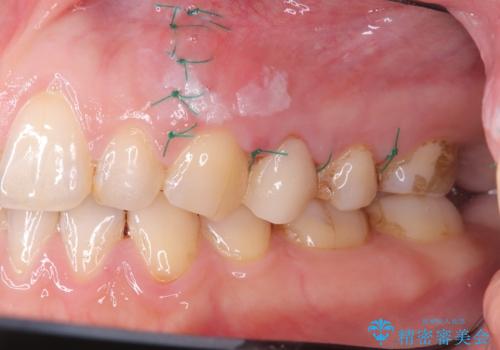

結果、根管内にはイスムスにデブリが多く見られたものの破折線は確認できませんでした。再根管治療後、症状の経過を3ヶ月ほど確認しましたが打診、違和感が消失しておらず、外科的歯内療法を行うこととなりました。

違和感という主訴に対しては、非歯原生疼痛の可能性も考慮し、専門医院への対診を優先して行うことがありますが、今回は打診が陽性だったため、患者さまの希望もあり外科を行いました。

結果、症状改善し治癒良好と判断できます。